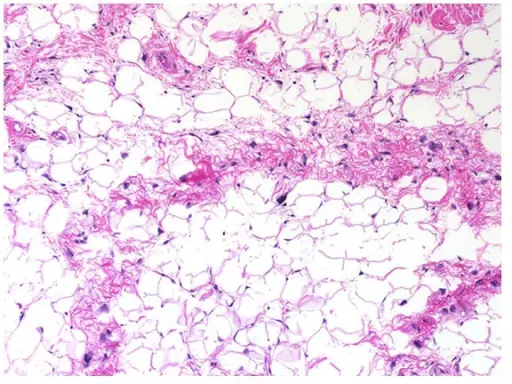

Definitive diagnosis of lipoma is made by pathology showing a well circumscribed mass composed of benign adipocytes.

Definitive diagnosis of liposarcoma is made by pathology showing malignant proliferation of adipose tissue.

Lipoblasts are the characteristic cells seen in liposarcoma.